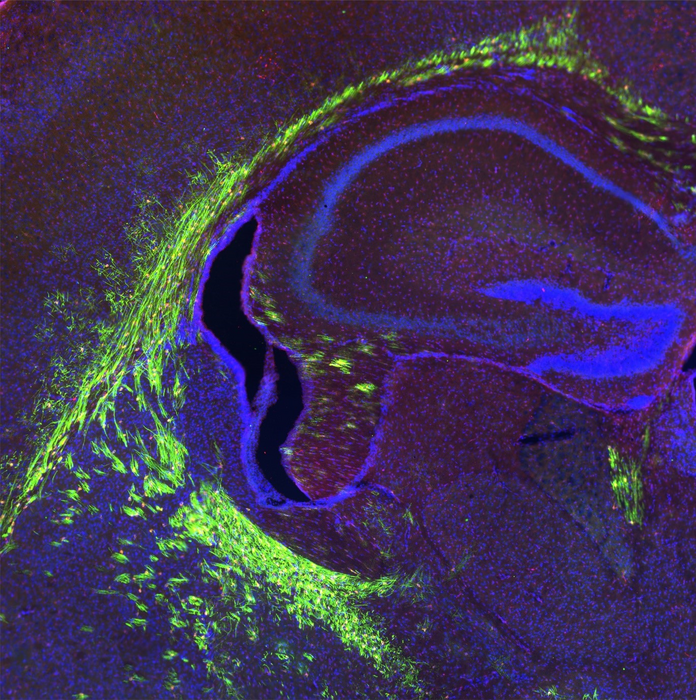

图:发育中的临床前模型大脑,有髓鞘轴突(绿色部分)

图片来源:Vetrivel Sengottuvel博士